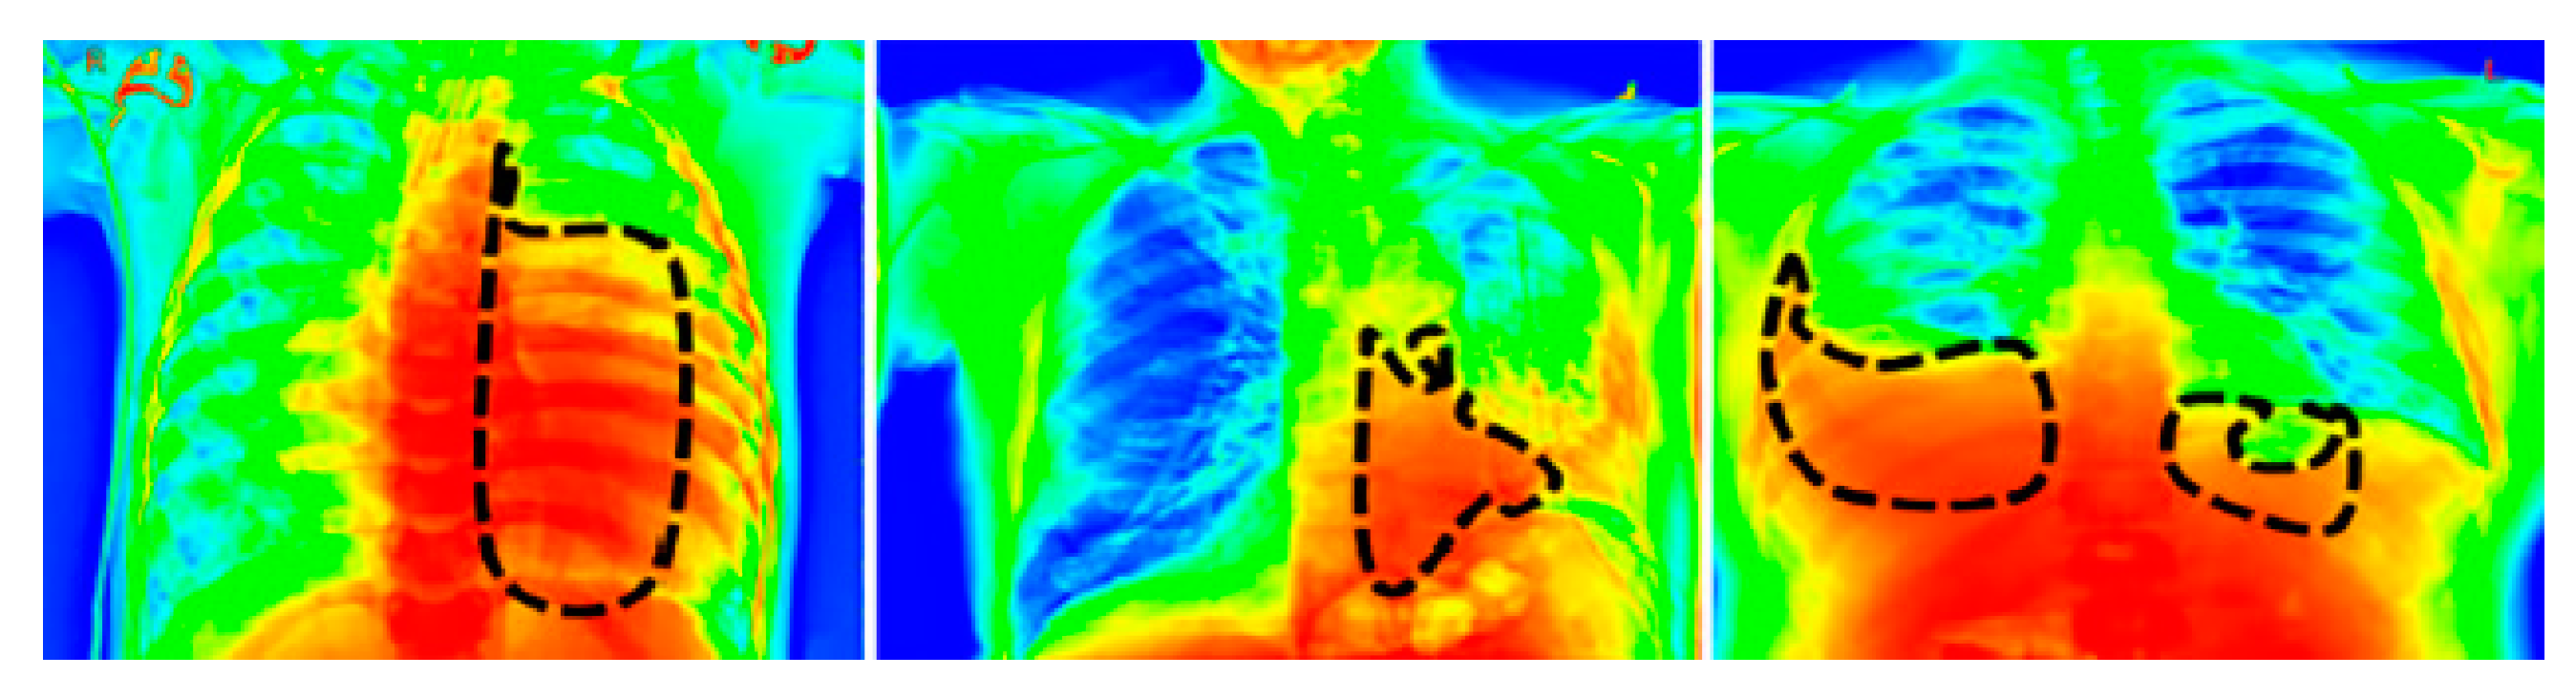

- We proposed a channel optimization technique (COT) to improve the quality of the input image.

3.2. Data Preprocessing